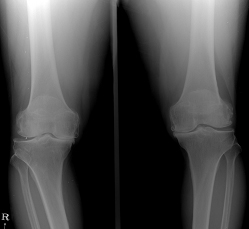

관절 건강에 도움이 되는 성분인 콘드로이친 입니다.나이가 들수록 뼈나 관절 등 신체기관들이 약해지는 건 어쩔 수 없죠. 특히나 무릎관절과 연관해서는 어르신분들이 많이 불편함을 호소하시는데요. 실제로 관절염 환자 중 60% 이상이 40~50대라고 해요. 그래서 최근엔 젊은 층에서도 관절건강에 대한 관심이 높아지고 있습니다. 이처럼 관절 통증 완화 및 연골 재생 효과가 있다고 알려진 콘드로이친 효능에 대해서도 알아보겠습니다.

콘드로이친 효능 1. 슬관절염 증상 완화

슬관절염은 슬관절의 연골 파괴와 염증으로 인해 발생하는 관절 질환으로, 통증, 염증, 강직성 등의 증상을 유발해요. 콘드로이친은 슬관절염 환자에서 통증 및 염증을 개선하는 데 도움이 돼요.

콘드로이친 효능은 연골 조직의 주요 구성 요소 중 한가지인 콘드로이틴 성분을 함유하고 있어요. 콘드로이친은 연골 조직의 재생과 보호에 기여하고, 슬관절의 염증을 줄이는 데도 효과가 있어요. 슬관절염 환자들이 콘드로이친을 복용하면, 연골 조직이 보호되어 연골 파괴가 줄어들고, 염증이 감소해서 슬관절 통증이 완화될 수 있어요.